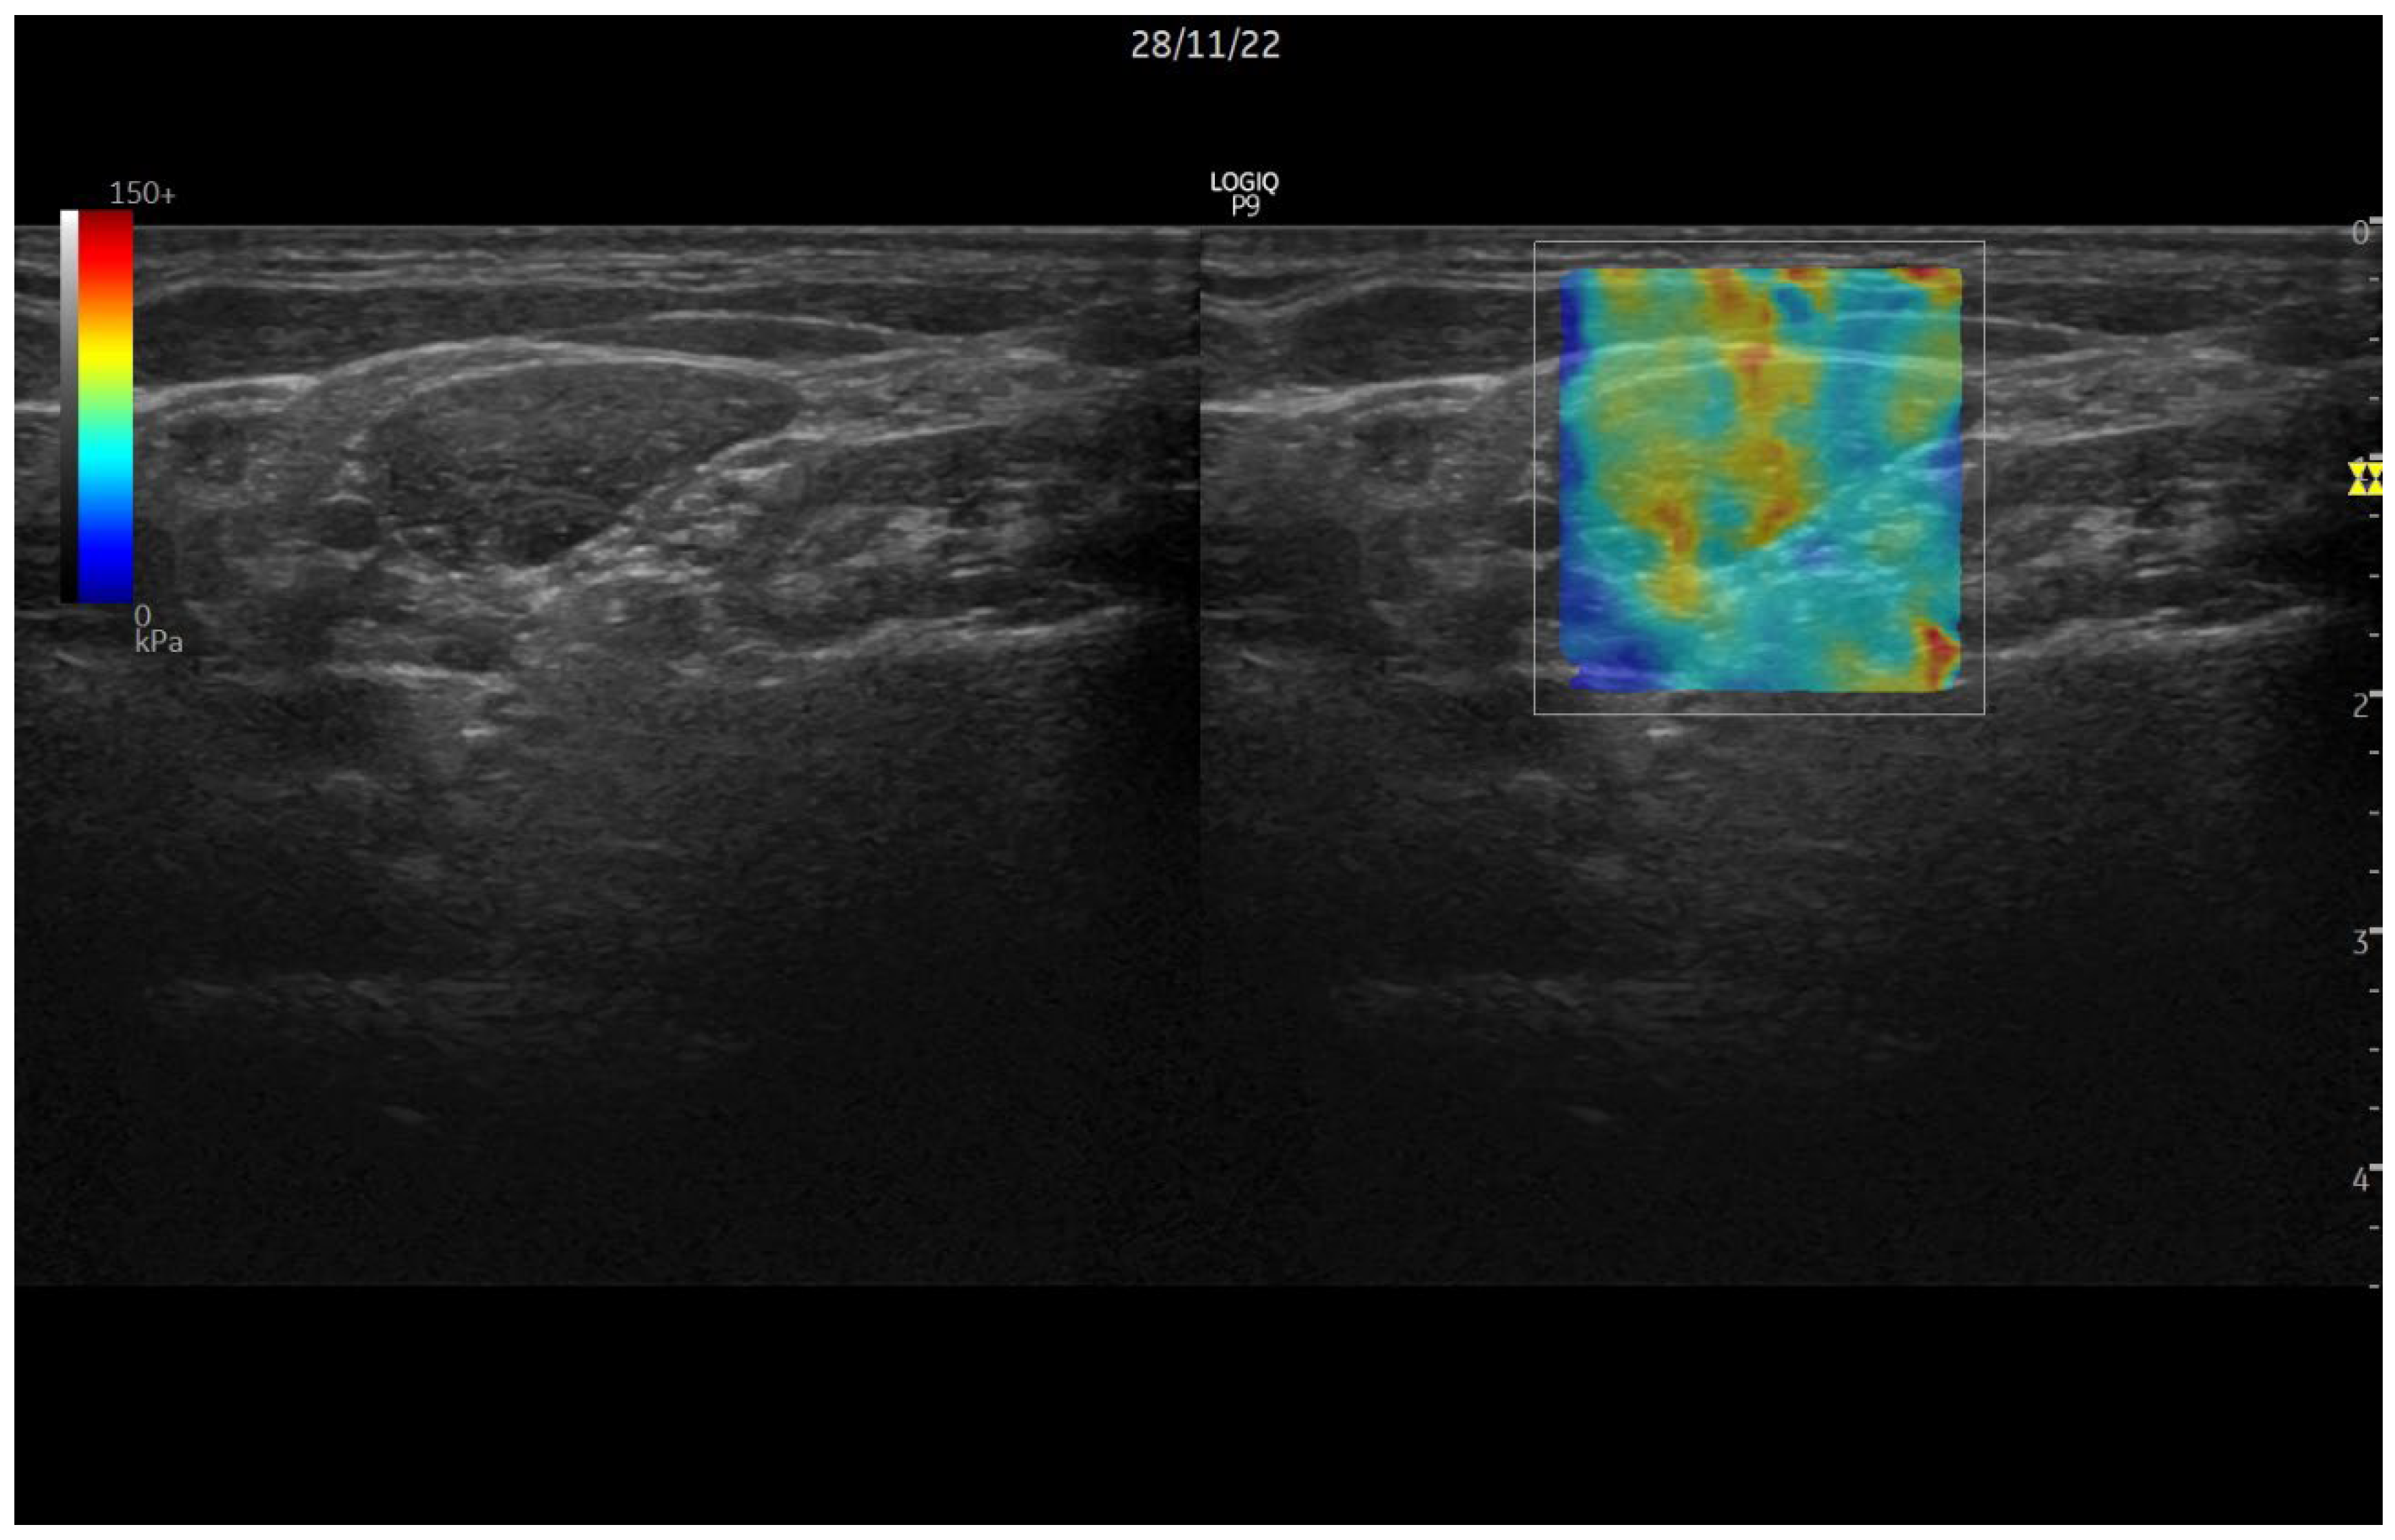

1.2. Ultrasound Elastography